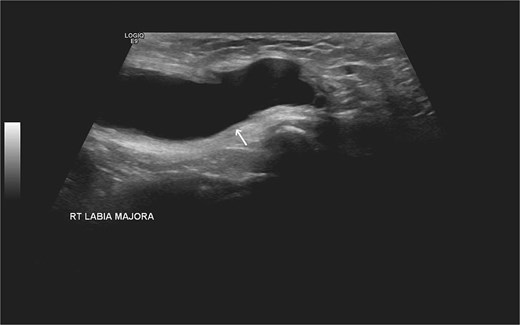

Laboratory studies, including complete blood count and comprehensive metabolic panel, were within normal limits. Initial ultrasonography (US) revealed an oblong cystic lesion with fine septations, measuring 6.5 × 3 cm, extending through the right inguinal canal into the labium majus (Figs 1 and 2). Subsequent pelvic magnetic resonance imaging (MRI) corroborated these findings, demonstrating a right lower abdominal cystic lesion with thin septations extending to the inguinal region, showing low T1 and high T2 signal intensity, measuring ~7 × 3.5 cm (Figs 3 and 4). No evidence of bowel or omental herniation was observed, suggesting canal of Nuck hydrocele.

US of the right inguinal area showing oblong cystic lesion measuring 6.5 × 3 cm, extending through the right inguinal canal into the labium majus (arrow).